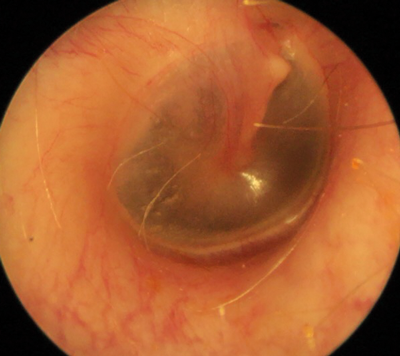

Cupris-TYM - otoscopy image.

Cupris - TYM

Type: Smartphone otoscope adapter for iPhone 5/6 Captures images + videos

Cost: £129

Image quality: 32%

Field of view: 42%

Ease of use: 58%

Comments: The images taken were mostly too dark and lacking in colour (tested with iPhone 6s). The picture was too zoomed in, due to a poor field of view, which made it difficult to navigate the tympanic membrane and get representative images. This product does have the advantage of not requiring any additional equipment, such as endoscopes or light sources, which is useful in low resource settings [1].